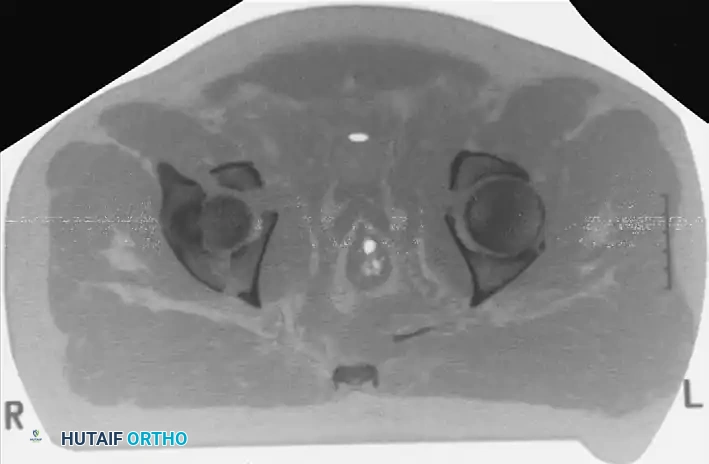

Secondary Congruence in Both-Column Fractures

A unique phenomenon observed exclusively in both-column fractures is "secondary congruence." Because all articular fragments are detached from the axial skeleton, they can occasionally settle concentrically around the medially displaced femoral head.

If the articular cartilage space is preserved and the femoral head remains concentrically enveloped by the fragments (despite medialization of the entire joint complex), nonoperative treatment via skeletal traction can yield surprisingly excellent long-term functional results.

Incarcerated Intra-Articular Fragments

Following the closed reduction of a hip dislocation, a post-reduction CT scan is mandatory. While small avulsions of the ligamentum teres sequestered deep in the cotyloid fossa may be observed, any osteochondral fragment lodged between the articulating surfaces of the femoral head and the acetabular dome necessitates urgent surgical excision and joint irrigation.